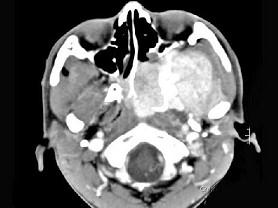

男性,19岁,左侧鼻腔反复出血一年余,CT、MRI扫描如图所示,请选择最可能诊断 ( )

答案: E